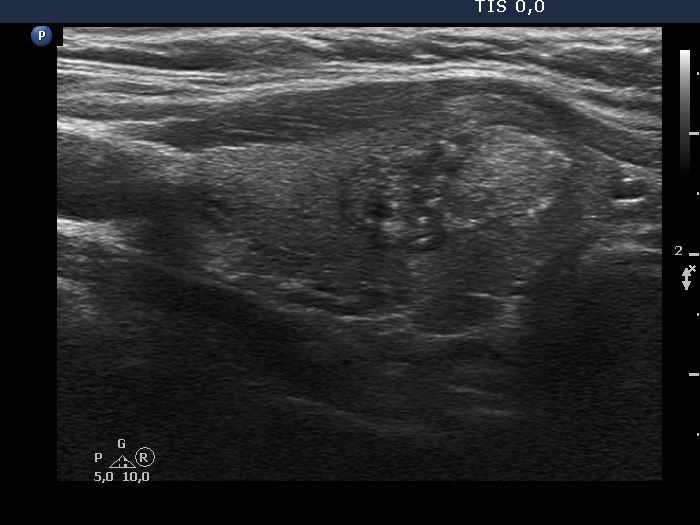

100 consecutive cases of papillary cancer - case 075 (ultrasonographic picture 6)

Right lobe, another longitudinal scan.